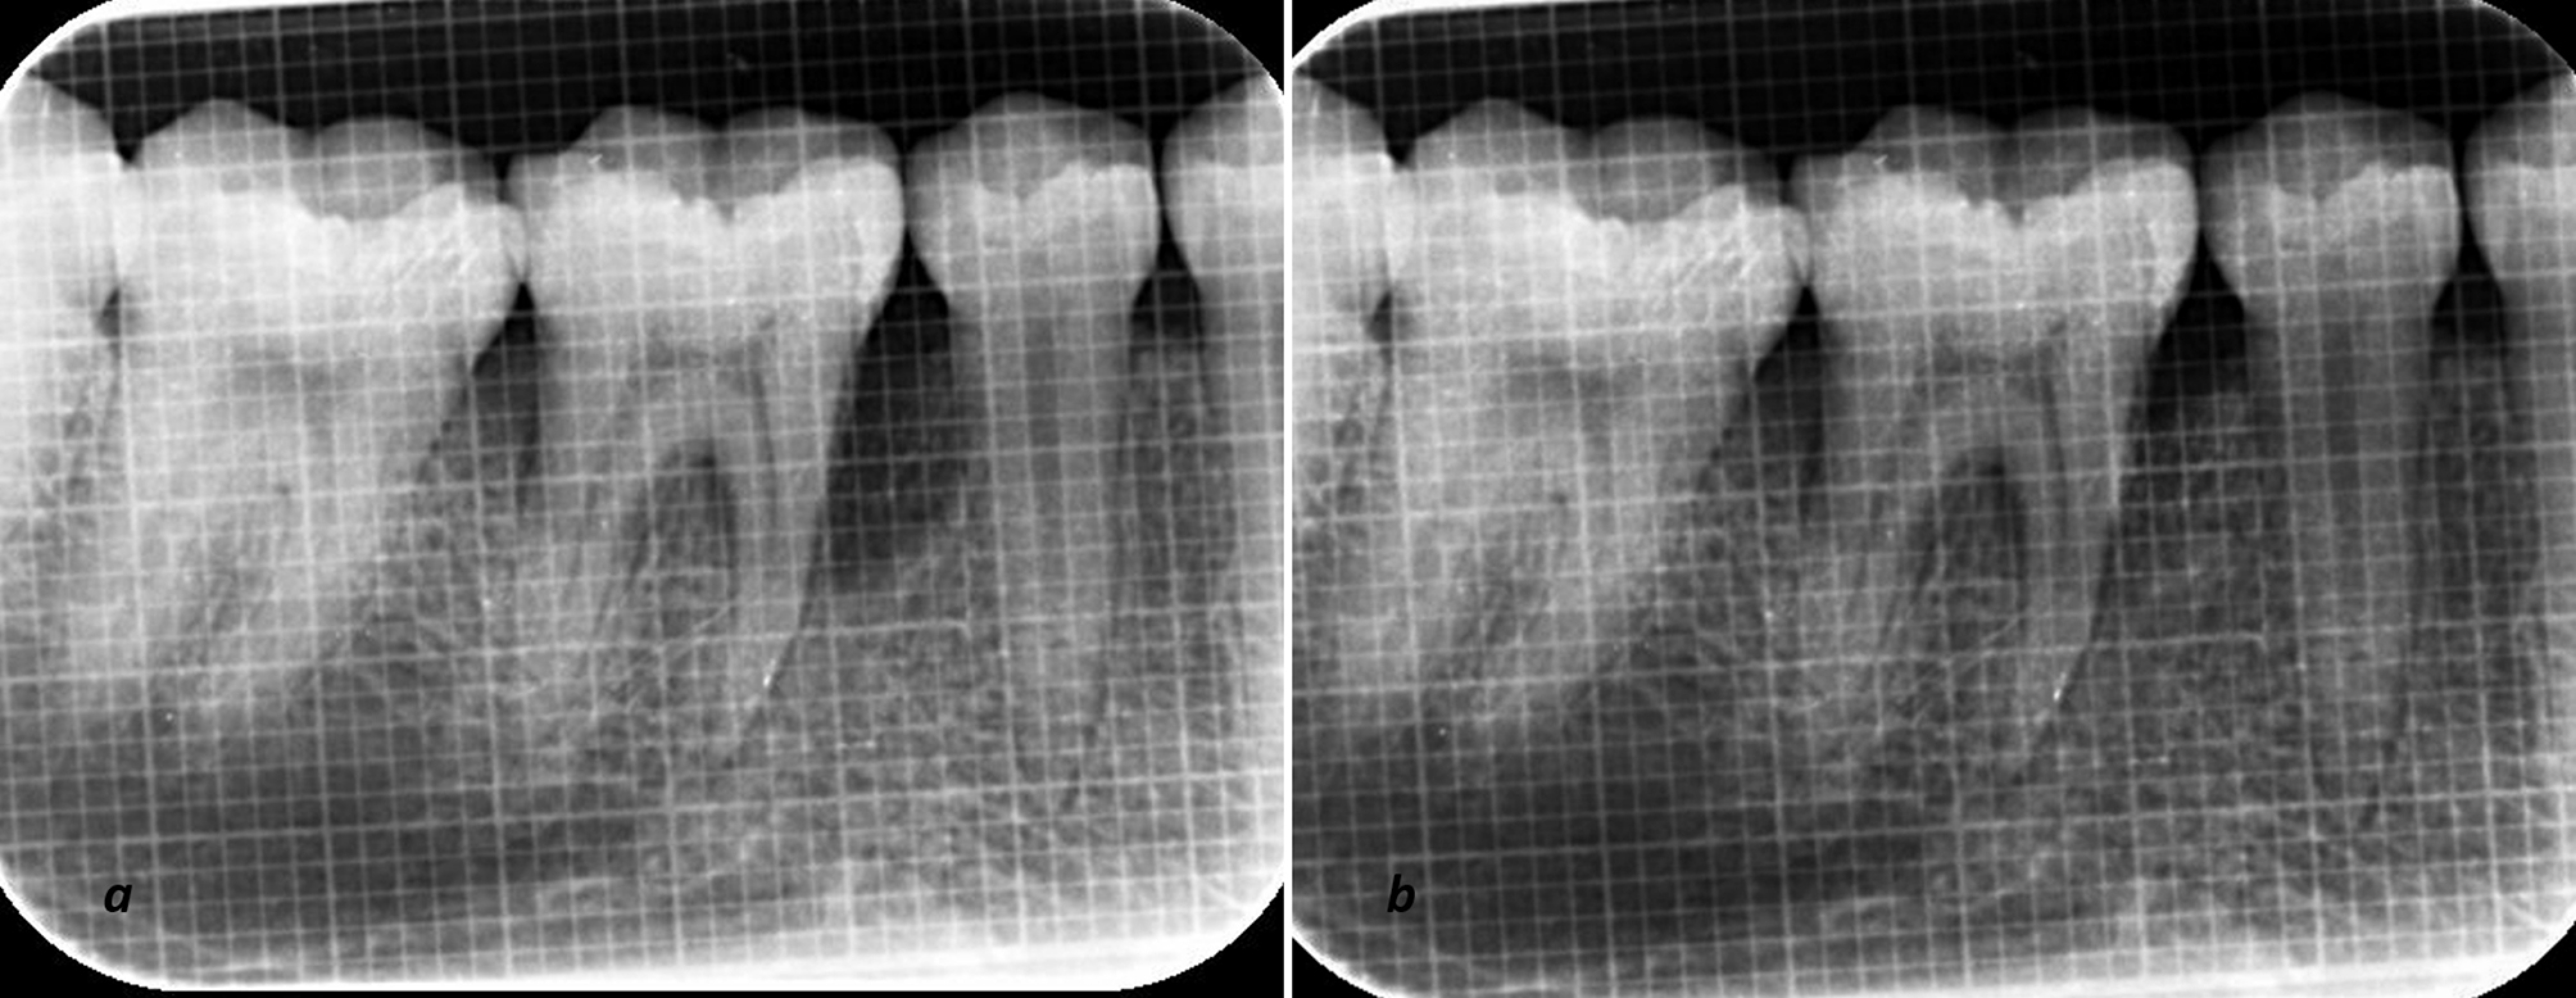

Radiographic parameters assessment

Uniformity regarding radiographs was obtained with a long-cone paralleling technique with Rinn’s film holder and a radiographic grid of 1×1-mm framework (Figures 3 and 4). An effort was made to take pre- and postoperative radiographs at a similar projection geometry and optical density. The images were scanned, and measurements, such as cementoenamel junction (CEJ) to the base of the defect (BOD) for defect fill and alveolar crest (AC) to BOD for resolution of defects, were evaluated at baseline and nine months postoperatively based on Meffert et al,21 and using ImageJ software (Wayne Rasband, National Institute of Health, USA).

The radiographic (IOPA) evaluation at baseline (a) and after 9 months (b) in the T-PRF group.